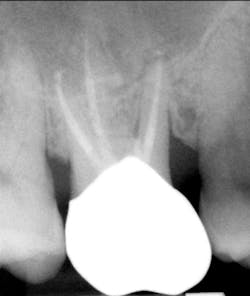

A 69-year-old male with a noncontributory medical history presented with 5 mm of recession, less than 1 mm of attached gingiva, and cervical notching on tooth No. 3. The tooth had an existing gold onlay and was caries-free (figures 1a and 1b). Radiographic analysis showed periodontal bone loss and a radiolucency at the apex of the tooth. The patient denied implant therapy and wanted to save the tooth.

Nonsurgical endodontic therapy was completed within two weeks, and the patient ultimately received a full-coverage restoration (figure 11). The patient exhibited normal, uneventful postoperative healing.

The pathology report identified the specimen as a 1.1 x 0.8 x 0.5 cm inflammatory cyst of the maxilla (figure 12). The patient now exhibits 10 mm of attached gingiva on the facial of tooth No. 3. The recession defect has been completely eliminated by a combination of the SECT graft and the full-coverage restoration (figure 13). The periapical radiograph shows no residual periapical pathology. After one year, the patient continues to be asymptomatic and is functioning well with the tooth.